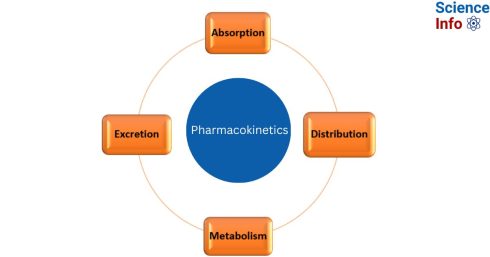

فارماکوکینتیک: جذب، توزیع، متابولیسم، دفع

مقدمهای بر فارماکوکینتیک فارماکوکینتیک، فرآیندی است که طی آن داروها وارد بدن میشوند، از آن[بیشتر بخوانید]